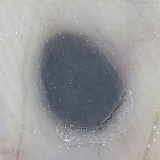

Внешне голубой невус Ядассона–Тиче представляет собой небольшого размера (до 8–10 мм в диаметре) плоскую или слегка приподнятую над кожей родинку. Поверхность такой родинки гладкая, без явной бугристости. Цвет может варьировать от голубого до тёмно-синего, причем окраска неравномерная из-за достаточно глубокого залегания образующих опухоль меланоцитов. В некоторых случаях размер невуса больше стандартного — до 3–3,5 см. Контур невуса не всегда четкий. Форма бывает круглая, вытянутая или веретенообразная. Ни равномерность окраса, ни форма родинки не является указателем на необходимость удаления или отсутствие такой потребности.

Клеточная форма отличается от неклеточной размерами — родинки такого типа в диаметре не менее полутора сантиметров. Из-за неоднородной по насыщенности окраски и часто встречающейся бугристой «рыхлой» поверхности его можно принять за меланому, формы которой могут иметь схожий набор признаков. Наиболее часто встречающиеся места локализации такого невуса — поясница и ягодицы, реже — кисти и стопы.

Ставить диагноз должен только врач, самодиагностика при данном виде опухоли недопустима ввиду ее меланомоопасности. При диагностике голубого невуса прибегают к дерматоскопии. При помощи дерматоскопа врач может оценить границы невуса, однородность, глубину залегания меланоцитов. Последнее особенно важно, поскольку при нормальном течении этот тип родинки не обязателен к удалению — с таким невусом вполне можно жить, если он не мешает и не изменяется.